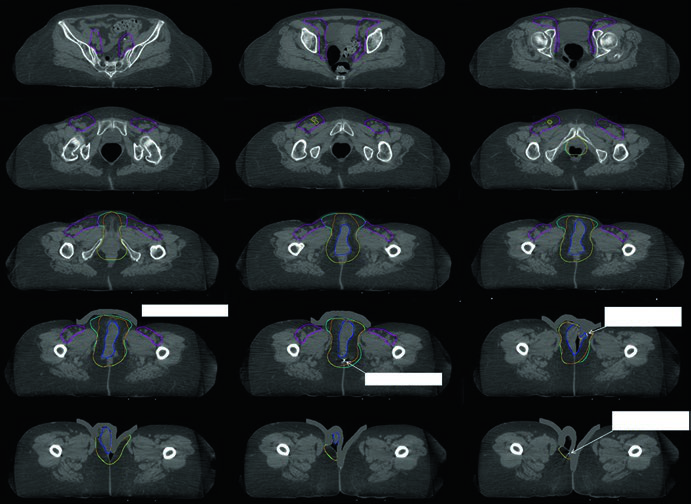

As figuras do capítulo ajudam a traduzir essas regras em decisões concretas. Na radioterapia definitiva da Fig. 23.1, a paciente tinha estádio FIGO IIIB, doença confinada à vulva considerada irressecável pela proximidade com meato uretral e vagina e dois linfonodos inguinais direitos avidamente captantes no PET. O GTV primário foi contornado em azul; o CTV1, em ciano, cobria toda a vulva com exclusão de osso e músculo adjacentes; o CTV2, em magenta, abrangia linfonodos pélvicos e inguinofemorais. Já a Fig. 23.2 mostra o cenário pós-operatório em uma paciente com estádio FIGO IIIA, margem patológica de 7 mm e um linfonodo inguinal esquerdo não sentinela de 3 cm comprometido sem extensão extranodal. Nessa situação, pelve e região inguinofemoral direita receberam 45 Gy, a vulva 50 Gy e a região inguinofemoral esquerda 55 Gy, tudo em 25 frações, com expansões de 5 mm por causa do CBCT diário.

A Fig. 23.3 acrescenta um ponto que costuma passar despercebido: mesmo entre especialistas em IMRT há variabilidade relevante no contorno. O consenso aparece em amarelo, o consenso modificado em vermelho e os contornos individuais de 14 médicos aparecem sobrepostos em dois casos, um localmente avançado e outro pós-operatório. O consenso modificado foi retraído do espaço entre vulva e virilha e também da superfície cutânea quando essas áreas foram consideradas de baixo risco. Em outras palavras, reduzir volume é possível, mas apenas quando o raciocínio de risco é explícito.